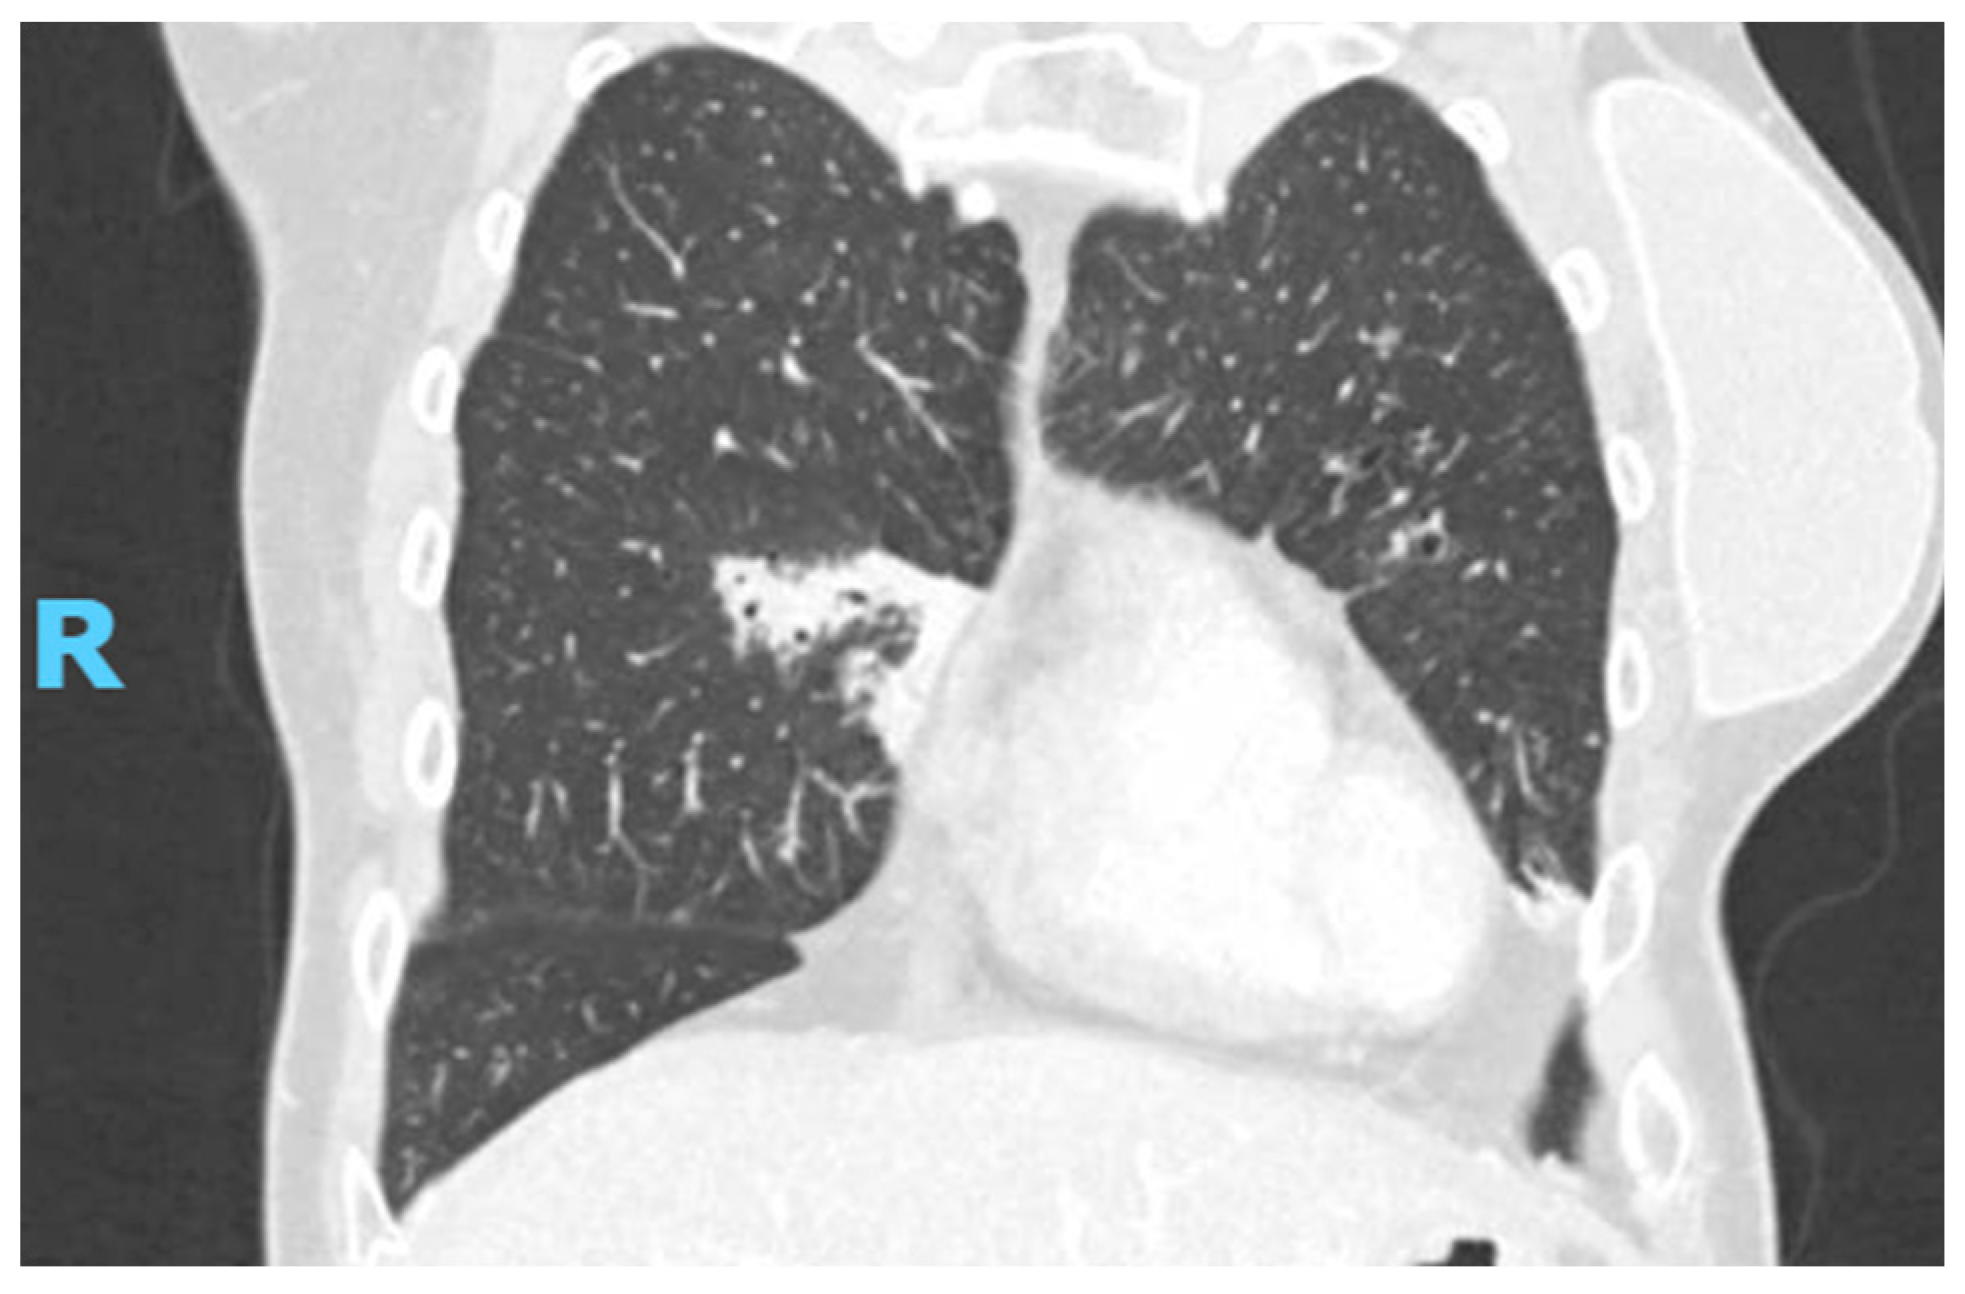

2. Case Presentation

2.2. Diagnostic Studies